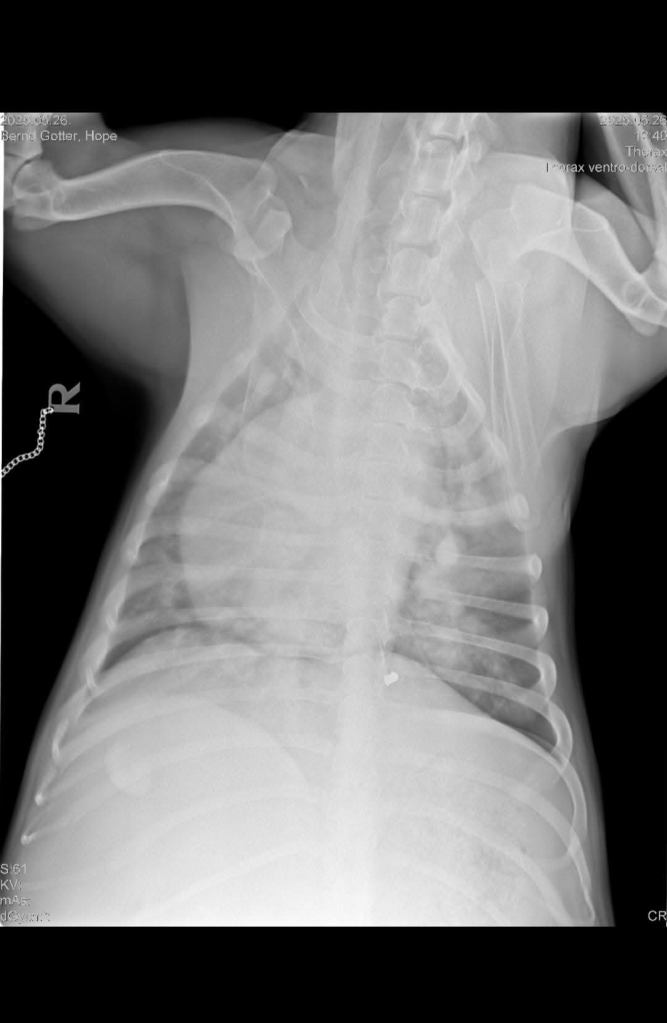

Wir hatten gestern Abend einen Videocall mit Hopes Besitzerin. Am Montag wurde Hopes Lunge geröntgt und ihr Herz wiederholt geschallt. Die ursprünglich geplante Herz OP wurde aufgrund neuer Erkenntnisse abgesagt. Hope hat weiterhin Wasser im Bauch, ihre Lunge arbeitet sehr schlecht, wodurch Hope Schwierigkeiten beim atmen hat. Ihr Zustand ist kritisch, sie ist schwach und bekommt aktuell täglich 7 verschiedene Medikamente. In der Lungenarterie wurden Würmer entdeckt. Eine Entfernung der Würmer an dieser Stelle ist nicht möglich, da Hope verbluten würde. Für eine Narkose ist die Hündin derzeit nicht stabil genug und würde sie nicht überleben. Die rechte Herzkammer ist beschädigt und die Herzpumpe in ihrer Funktion auch sehr beeinträchtigt. Alles in allem sind die Gegebenheiten wirklich schwer, also gibt es zum jetzigen Stand nur die Möglichkeit rein medikamentös zu behandeln und die Würmer abzutöten. Eine OP ist nicht auszuschließen, sofern Hope stabil genug sein wird, doch das braucht Zeit und viel Glück. In der Hoffnung, dass die Medikamente ihr bestes tun, werden Hopes Herz und Lunge kommende Woche Mittwoch nochmal geröntgt und geschallt.

Leider wurden durch die Röntgenaufnahmen auch 2 Diabolos entdeckt, wovon eine an ihrer Rippe befindlich ist. Schlimm genug, dass Hope so schlecht behandelt und misshandelt wurde. Man hat auch noch auf sie geschossen! Die andere Patrone sitzt sehr ungünstig in der Nähe der Wirbelsäule und muss ggf. entfernt werden, was aber auch gewisse Risiken mit sich bringt!